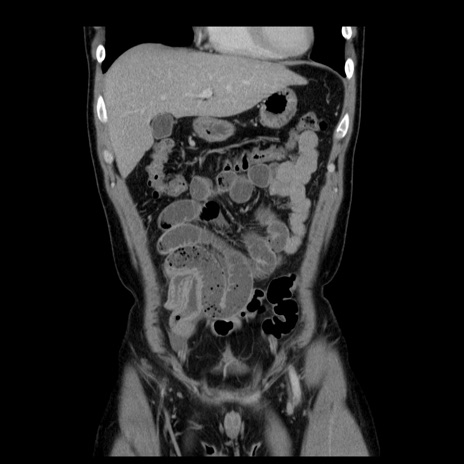

横断像

【症例】30歳代男性

【主訴】腹痛、嘔吐

【現病歴】昨晩から突然の腹痛あり、その後嘔吐、軟便も出現。腹痛が改善しないため救急搬送となる。2日前にしめ鯖の食事歴あり。

【身体所見】意識清明、苦悶様、BP 135/90mmHg、BT 35.7℃、腹部:平坦、やや硬、心窩部〜臍部に自発痛、圧痛あり、筋性防御+、反跳痛-

【データ】WBC 8100、CRP 0.57